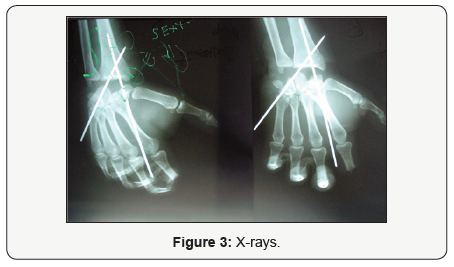

We present a case of 34 years old right/hand/dominant male patient was injured in December 2007 with the cutting metal machine in an aluminum manufacturing factory about 200 miles away from Belgrade. He arrived at our Trauma center 4 hours after being injured, conscious, communicative and well oriented. The amputated hand was brought in a nylon bag placed in a small mobile refrigerator filled with ice cubes. After clinical and radiological examination of the amputated hand, the patient was accepted for hand replantation [3] (Figure 1). In preparation for the surgery radiographs were taken and they revealed amputation at the midcarpal level, intravenous fluids and tetanus immunoglobulin were administered as well as antibiotics, combination of ceftriaxone sodium, gentamicin and metronidazole by intravenous infusion, starting at the time of admission to the hospital. Anti-tromboembolic prophylaxis was also administered using low molecular weight heparin, Fraxiparine (Figure 2). Careful lavage of both amputated hand and proximal wrist with more than three litres of natrium-sodium solution was obtained followed by careful examination of both anatomical regions. Tourniquet was applied, necessary bone shortening, in this case we found to be possible only with first row carpectomy, performed and followed with stabilization with two 3.2mm Steinman pins. Because of better functional postoperative status and uninjured distal radius articular surface we have decided not to shorten distal radius or distal carpal bones. Soft tissue debridement was conducted together with identifying of arteries, veins, nerves and tendons (Figure 3). Superficial flexor tendons were also debrided. Radial artery was first anatomical structure to be sutured, followed by reconstruction of flexor tendons, both radial and ulnar nerve, extensor tendons and only one vein [4-6] (Figure 4).